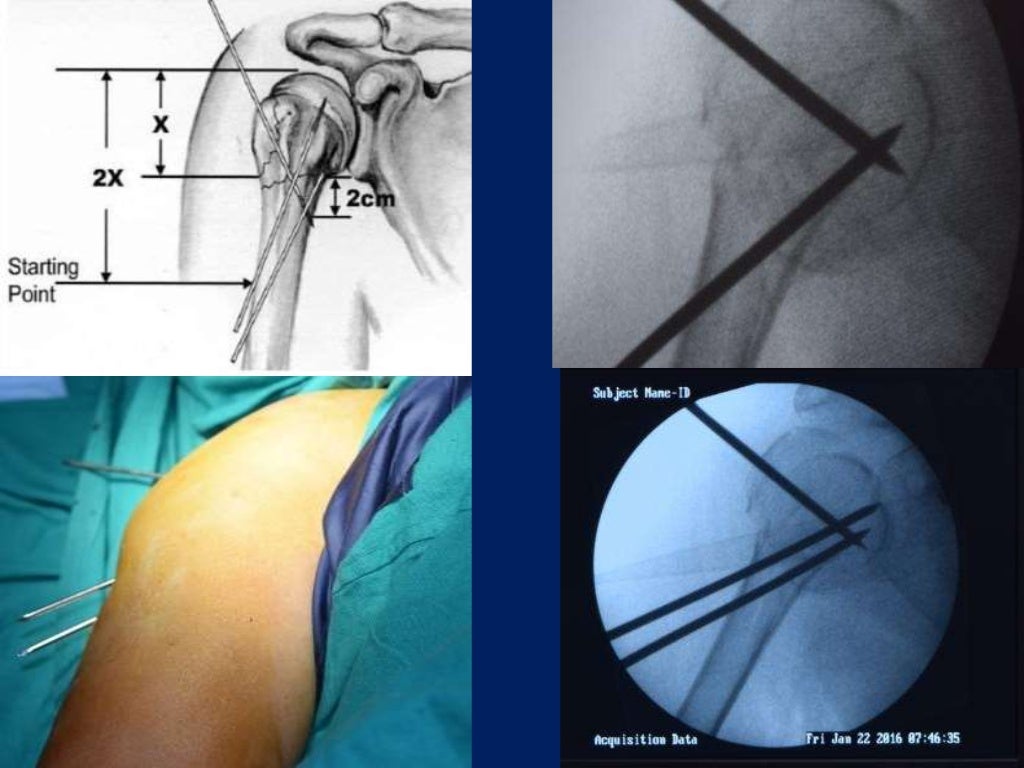

Fracture proximal humerus Fixation with K wires and External fixator What Is K Wire Surgery Learn about the types, sizes, indications, techniques and complications of k wire in orthopedics and other surgeries. Find out how to choose the size, direction, and entry point of k. k wires, also known as kirschener wires, are used to hold a broken bone in the correct position following. k wire is a metallic wire used to hold. What Is K Wire Surgery.

(A) Surgical setup and demonstration of the kwire insertion. (B) View What Is K Wire Surgery k wire is a metallic wire used to hold bone fragments together or provide an anchor for skeletal traction. Find out how to choose the size, direction, and entry point of k. Find out the principles, anatomy, diagnosis,. k wires, also known as kirschener wires, are used to hold a broken bone in the correct position following. Learn. What Is K Wire Surgery.